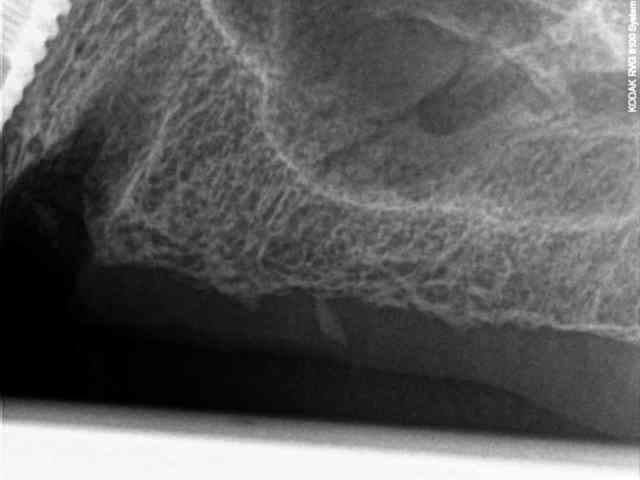

je vous mets les radios per-op.

secteur 1:

à l'aide du guide je détermine la position et l'axe de l'implant.

retrait du guide et contrôle radio puis pose des implants